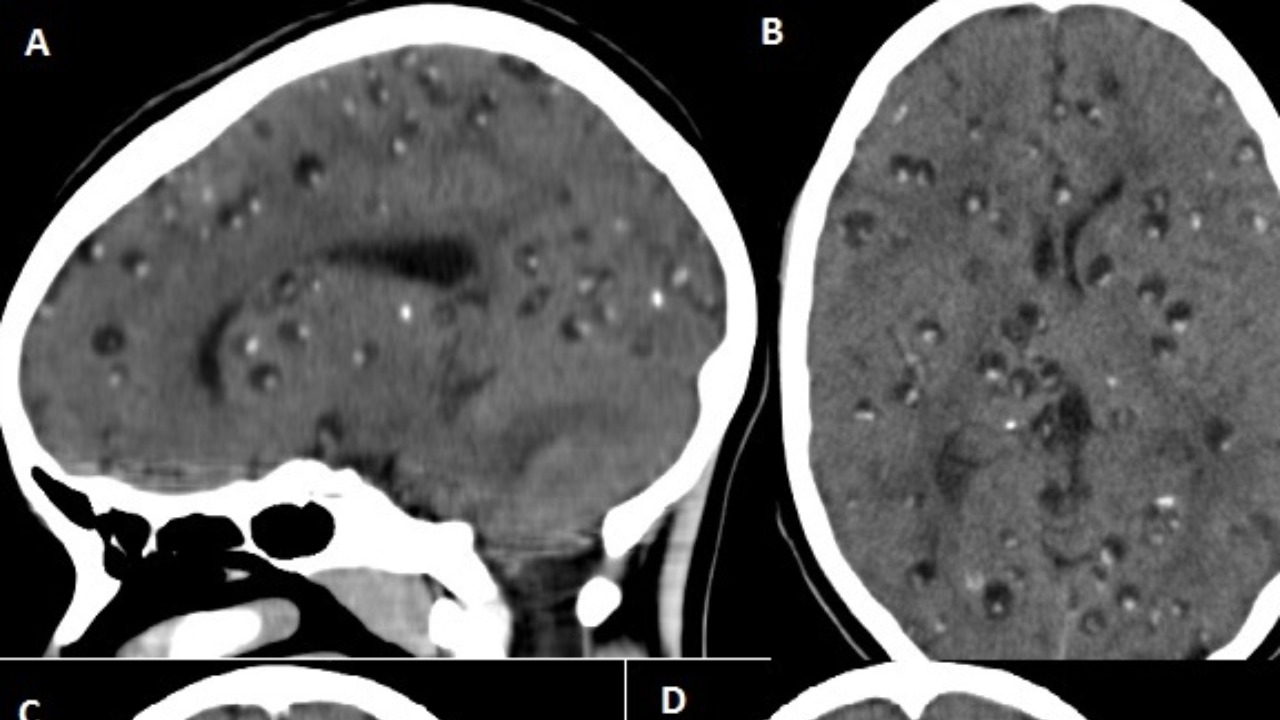

The research, led by a team of Swedish scientists, utilized advanced imaging techniques and methodologies to study the human brain. With this approach, the team was able to confirm the continuous production of new brain cells in adult humans. This discovery stands in stark contrast to the previously held belief that brain cell production, or neurogenesis, ceases in adulthood.

Neurogenesis is the process by which new neurons, or nerve cells, are formed in the brain. This process was previously thought to occur only in certain periods of life, particularly during prenatal development and early childhood. However, the recent discovery has shown that neurogenesis can continue well into old age, providing a new perspective on the brain’s capacity for growth and change.